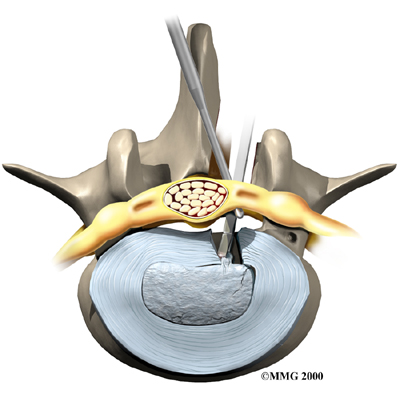

Microdiscectomy

Microdiscectomy is becoming the standard surgery for lumbar disc herniation. The procedure is used when a herniated disc is putting pressure on a nerve root. It involves carefully taking out part of the problem disc (discectomy). By performing the operation with a surgical microscope, the surgeon only needs to make a very small incision in the low back. Categorized as minimally invasive surgery, this surgery is thought to be less taxing on patients. Advocates also believe that this type of surgery is easier to perform, that it prevents scarring around the nerves and joints, and that it helps patients recover more quickly.

Related Document: FYZICAL Rockville's Guide to Lumbar Discectomy